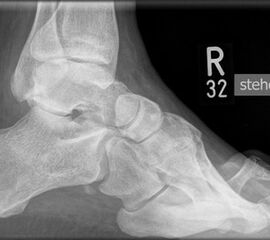

• Fuß belastet dp und seitlich (Abb. 14 und 15)

• Saltzman view (Abb. 16)

Typische Merkmale der Standard-Seitaufnahme des Fußes im Stand

• Knöchelgabel ist außen rotiert

• Talus und Calcaneus verlaufen fast parallel

• Sinus tarsi ist einsehbar

• Subtalare Gelenklinie verläuft horizontal und ist breit einsehbar

• Der Abstand Malleolus medialis zum Os naviculare ist verkürzt

• Der Calcaneus erscheint verkürzt

• Der Krümmungsscheitel des Fußes ist erhöht

• Calcaneus pitch ist meist erhöht, der Rückfuß Equinus ist eher selten 12